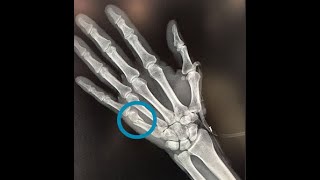

Fractura 5 Metacarpiano Sin Desplazamiento, FRACTURA DEL BOXEADOR FRACTURA DEL QUINTO METACARPIANO CAUSAS SÍNTOMAS Y TRATAMIENTO, 10.78 MB, 07:51, 88,472, Dr.Bernardo Velasco, 2021-07-09T00:46:10.000000Z, 3, An x-ray showing the metacarpal bone fracture at right fifth bone of, www.researchgate.net, 715 x 861, png, WebSi es una fractura simple, sin gran desplazamiento y sin cambio de ángulos (de modo que no haya acortamiento), no será necesario intervenir. Plazos de. WebGeneralmente, el tiempo de recuperación de una fractura del quinto metacarpiano se enmarca entre 3 y 6 semanas tras el traumatismo. En personas activas, con un trazo. WebEn los casos de fractura del quinto metacarpiano, se aplica un tratamiento conservador cuando la fractura ocurre por debajo de la cabeza del., 20, fractura-5-metacarpiano-sin-desplazamiento, Novedades y Muebles WebSi es una fractura simple, sin gran desplazamiento y sin cambio de ángulos (de modo que no haya acortamiento), no será necesario intervenir. Plazos de. WebGeneralmente, el tiempo de recuperación de una fractura del quinto metacarpiano se enmarca entre 3 y 6 semanas tras el traumatismo. En personas activas, con un trazo. WebEn los casos de fractura del quinto metacarpiano, se aplica un tratamiento conservador cuando la fractura ocurre por debajo de la cabeza del.

WebHay veces en que existe una fractura sin desplazamiento, lo que puede confundirse con una contusión y que en el estudio de ésta se pesquisa que existe una fractura. Cuando. WebEl quinto metacarpiano es más comúnmente lesionado por el golpe (fractura del boxeador). Cuando estas fracturas resultan de golpear a alguien en la boca, la flora oral humana.

WebLa fractura del quinto se clasifica según la localización donde se produce la fractura. Tipo 1:Fractura de la tuberosidad: se produce por tracción del tendón peroneo corto a nivel. WebLa conclusión principal sería que las fracturas del cuello del 4º y 5º metacarpiano sin una deformidad rotatoria deben ser tratados con un vendaje adyacente. WebLa fractura subcapital más típica es la de la cabeza del 5º metacarpiano por un puñetazo contra la pared. Fractura transversa de metacarpiano. El trazo de fractura puede.